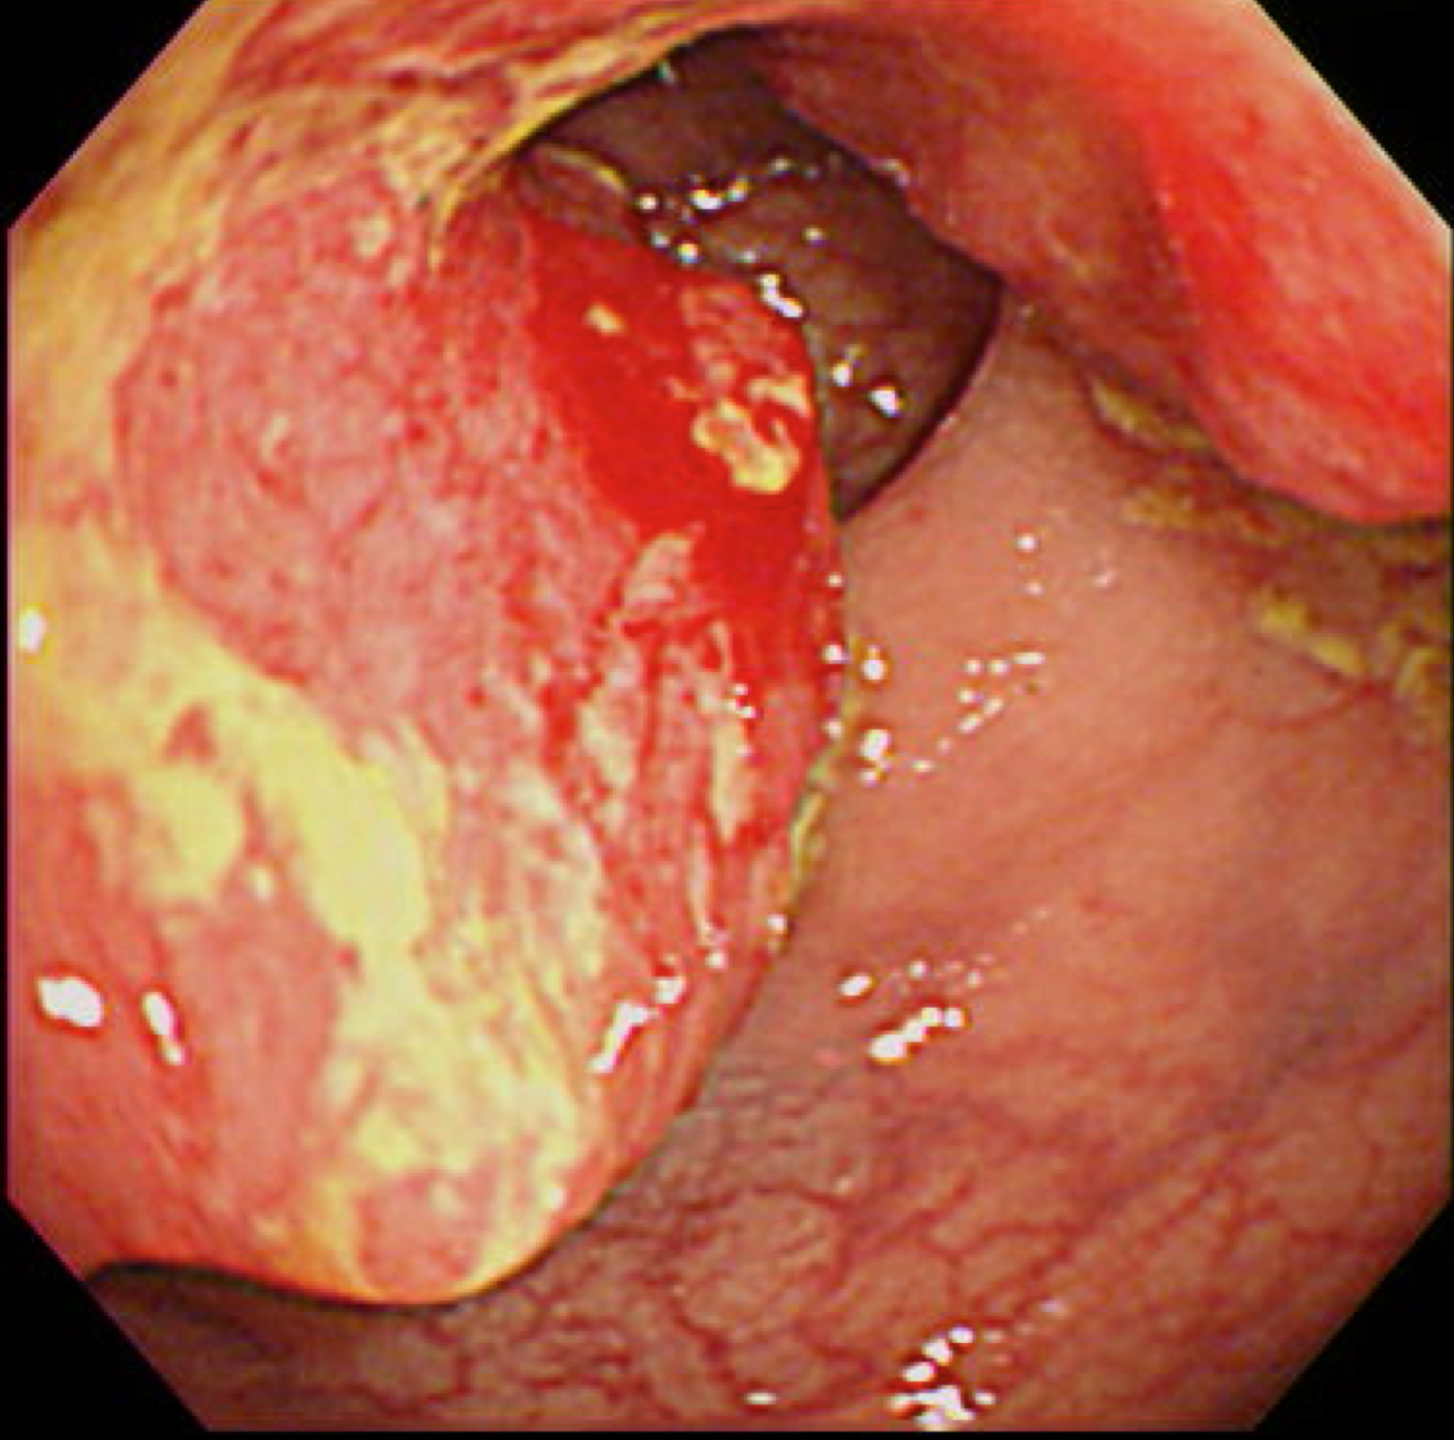

食道がん(上部消化管内視鏡)

胃がん検診

富山市の胃がん検診は胃内視鏡(上部消化管内視鏡)もしくは胃透視(バリウムを飲む検査)でおこなわれています。胃がんはかつては日本人にとって非常に多いがんでしたが、ヘリコバクターの保菌者の減少とともに、胃がんも少なくなりつつあります。

胃がん検診では喉頭部・食道・十二指腸上部を観察します。

当院では胃内視鏡(経口)のみを実施しております。胃の中を十分に検査するために高解像度の内視鏡を使用しており、そのため口からの内視鏡検査となります。一般的に鼻からの経鼻内視鏡による検査の方が楽な検査と言われていますが、内視鏡が細い分、最新型の経口高解像度内視鏡に比べて解像度が落ちます。

富山市からの検診の案内には経鼻内視鏡のできる施設が明示されていますので、ご希望に合わせて受診してください。